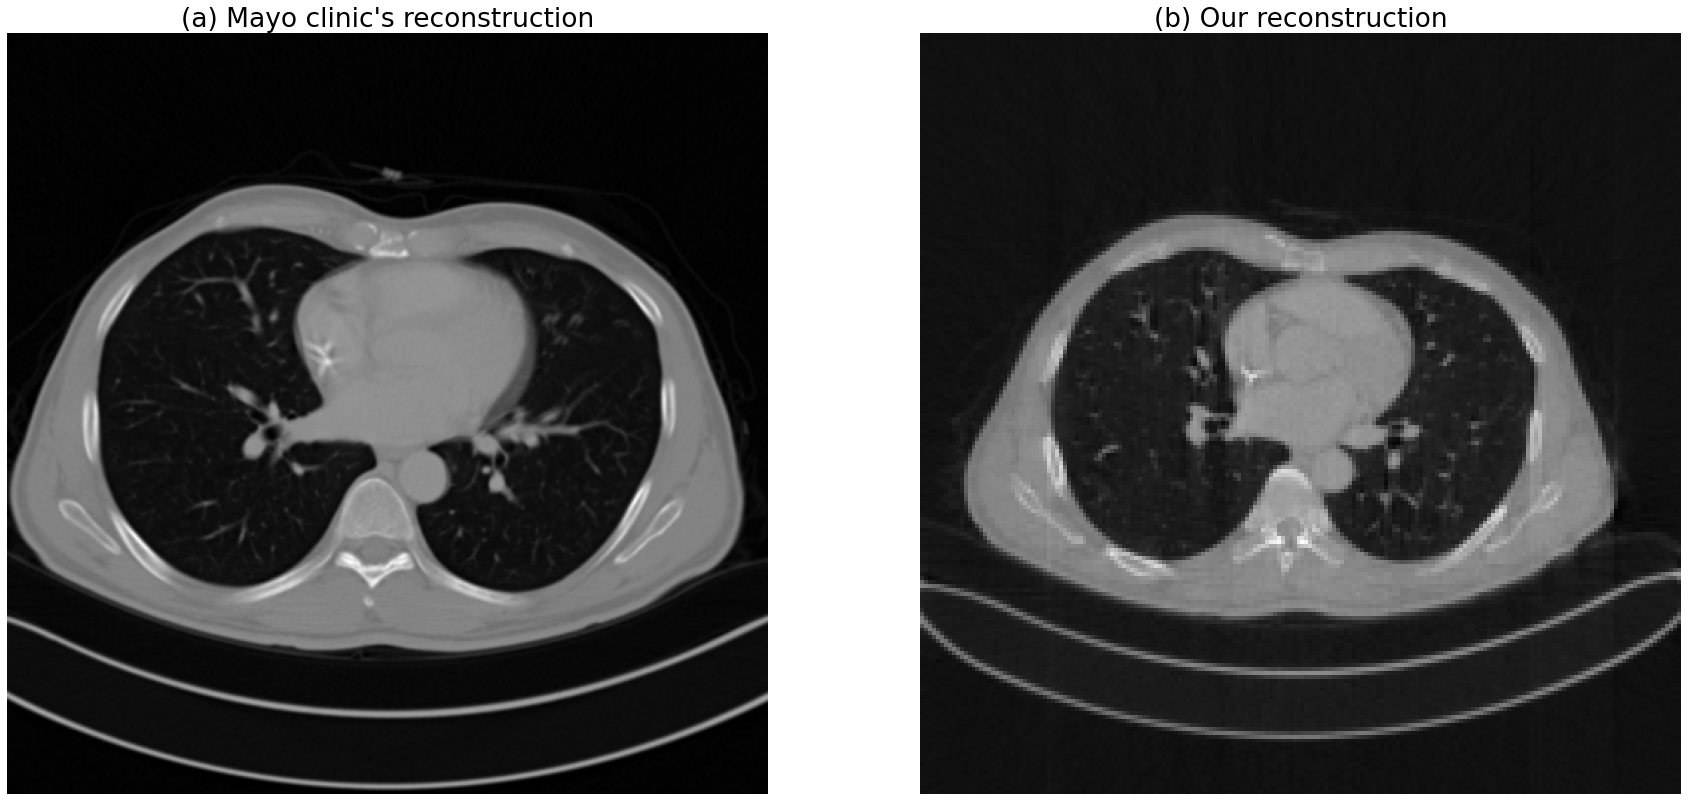

Refer to caption

Figure 4: Denoising results compared to other methods

Figure 4 shows the results from our approach and other methods pretrained with other CT images. the results can be compared to others.

We can find that JBFNet and this approach were robust to some points. It is because the others are basically based on image translation neural network models. However our approach and JBFNet learn parameters for filtering. therefore, it doesn’t get effected so much on the difference of geometries or image range, etc. Therefore, those approaches can have comparably robust results.

There is a proof for the image domain range issue in Figure 4. after matching the image domain range to how much the models are pre-trained with training dataset with. the images quality got better notably. it can be one of future benefits of using this approach. this method can be robust to any range of HUs so that it can be applied to general problems. before matching the domain, the metric values including PSNR and SSIM of the GAN-based models don’t look good, which means GAN-based models are over-sensitive to the image domain range and geometries of training data. and on the other hand, QAE, JBFNet, this approach are robust from image domain range issue.

the quality of the results was hard to be compared directly to mayo clinic reconstruction results. because as we can see in Figure 6, extra post-processing methods were applied to the volume obviously. and the reconstruction range is narrow than our results so it is also another reason to make it harder.